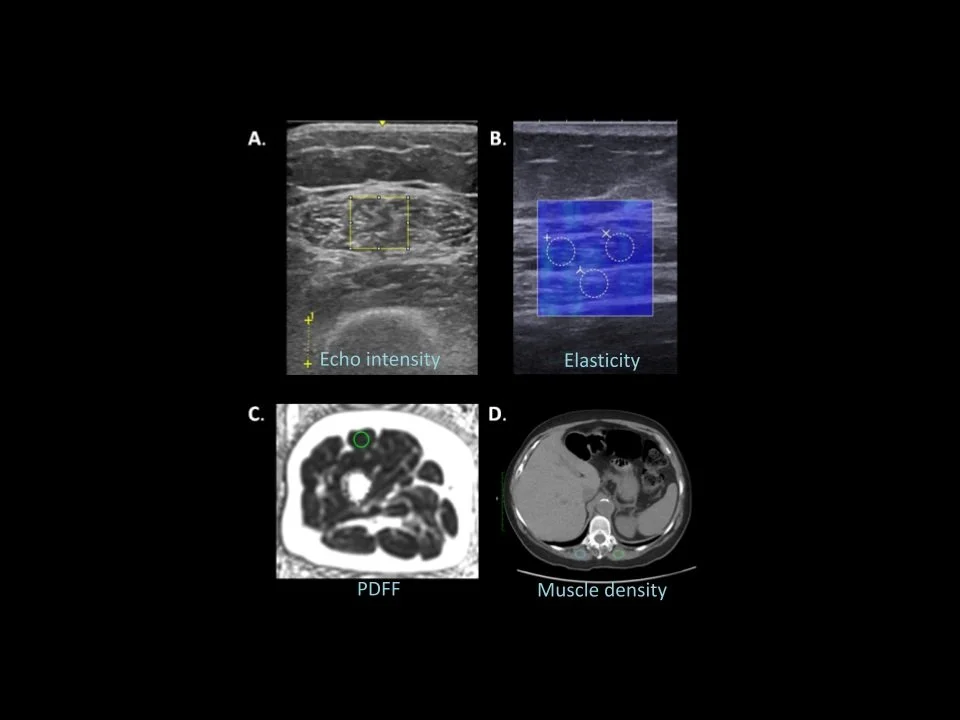

Ben has given these presentations.He’ll probably give them again if you’re interested. SciComm and AI AI for Scientists Humor and Science Strategic Science Communication Improv for Scientists Muscle Health Biomarkers